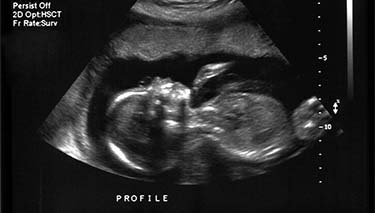

The ultrasound will pick up images of your baby's organs in a series of cross sections. This can be confusing at first, until you become used to the images and your eyes adjust. Your baby's bones will be white on the screen and the amniotic fluid will appear as black. Their tissues will be grey and have a speckled appearance.

Sonographers have a check list of what they need to look for when doing the 20 week ultrasound. They start off with the basics and work their way through a range of observations including:

- Checking how many babies are present. If this is your first scan it's important to know if you are carrying one or more babies.

- The lie or position of the baby.

- Your baby's spine and abdominal wall.

- The size, weight and general appearance of your baby.

- If the size of your baby is matching your gestational assessment.

- The position of the placenta and cord and the amount of amniotic fluid. If the placenta is assessed as lying low, a repeat ultrasound at 30 weeks gestation may be recommended.

- Your baby's brain, heart, lungs, stomach, oesophagus and trachea, kidneys and general anatomy.

- The limbs, the fingers and toes (counted) the facial appearance and lips/palate.

- Measurements of your baby's head, biparietal diameter, length and a measurement of their femur (long bone in the thigh) will also be taken. These measurements are compared with the average for babies of the same gestation.